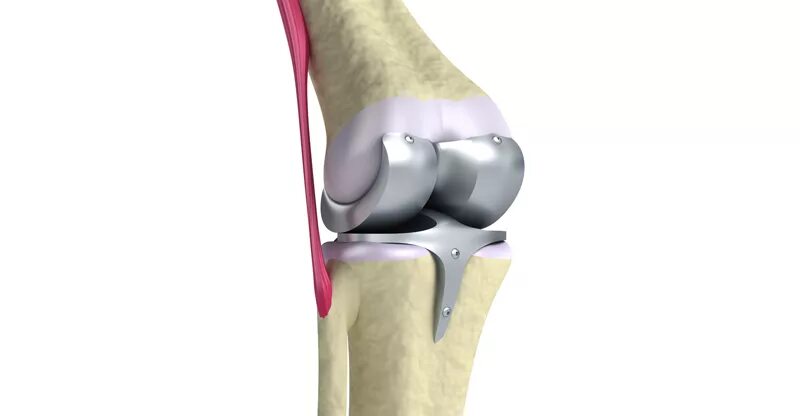

Как выглядит коленного